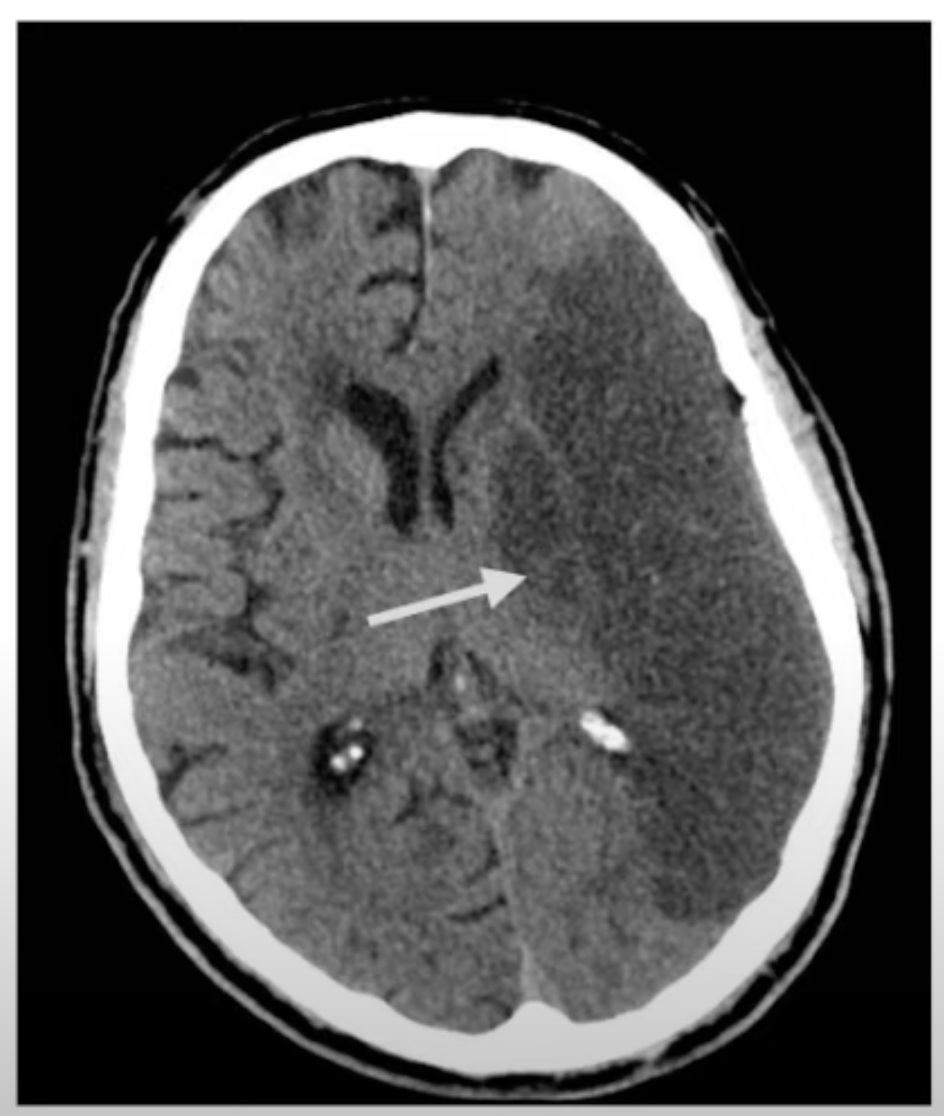

Se ve hipodenso

A

EVC isquémico

El dx de EVC isquémico es por sospecha clínica con base a los antecedentes, signos, síntomas y EF. Sin embargo, el gold standard es:

RNM y TAC para dx diferencial